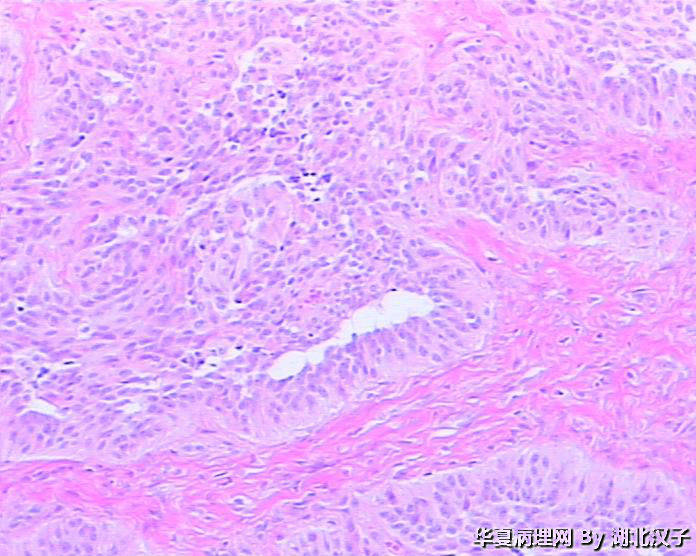

• 宫颈肿物图2

图2

48岁,宫颈肿物

有腺腔样结构,宫颈的上皮状态与图片有相关吗?似巢状浸润。

平滑肌瘤,富于细胞?

平滑肌瘤,富于细胞。

平滑肌瘤??

1、没见到正常宫颈组织;2、没见到肿瘤边缘,如果境界不清则不是平滑肌瘤。